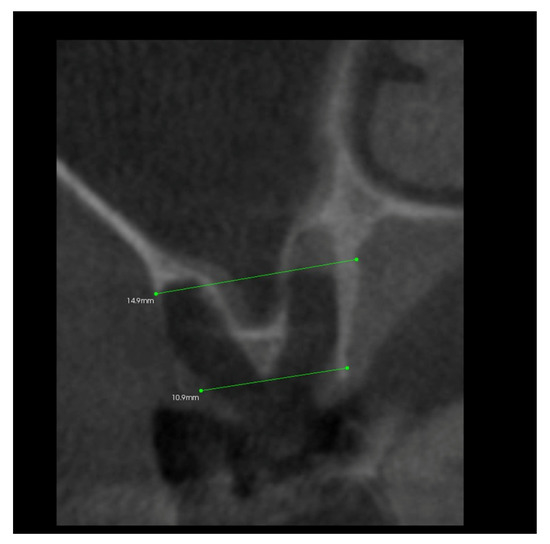

- The A line drawn through the apexes of the teeth adjacent to the post-extraction socket;

- The IC line drawn through the top of the buccal cusps of the teeth adjacent to the pos-extraction socket;

- The midline of the post-extraction socket (alveolus).

3.2. The Results of Mean Values of the Alveolar Process Width and Height Measurements Performed after Tooth Extraction within the Space of 6 Months for Two Different Alveoli in the Same Patient

3.4. The Results of Mean Measurements of Height and Width of the Alveolar Processes of Two Extraction Sites (with and without PRF) in the Same Patient after 6 Months from Tooth Extraction Based on the Analysis of Volumetric Tomography